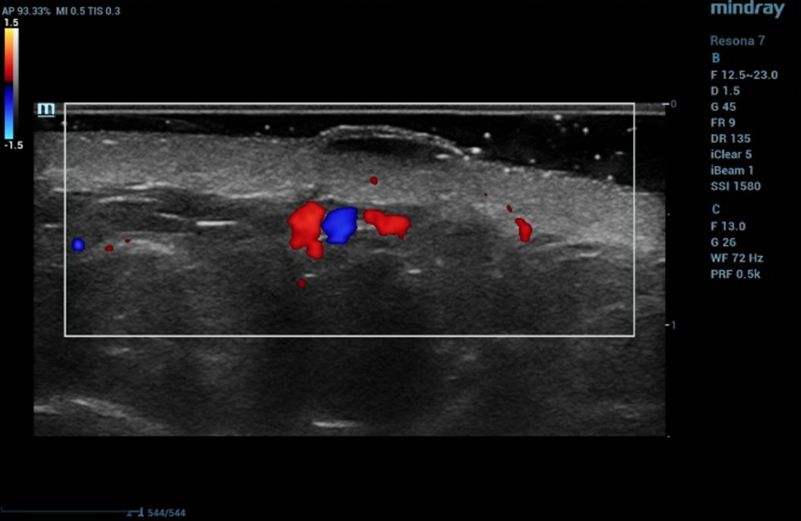

Ultrasound examination of the nevus was performed on the Resona 7 ultrasound machine (Mindray, China) using the high frequency linear transducer L20-5U (max frequency 23 MHz). When the transducer was placed in the projection of the visible nevus of the right zygomatic region of the face, the derma was locally thickened to 2.4 mm due to a hypoechogenic mass located under the epidermis and slightly elevated, spreading in depth to all layers of the dermis with clear rough boundary of heterogeneous echogenicity, without hyperechogenic sports, giving a weak acoustic darkening of the echo signal (Figure 2). Blood flow is not registered inside the nevus in the Color Doppler mode (Figure 3).

Ultrasound examination of the nevus in Color Doppler mode

Figure 3. Ultrasound examination of the nevus in Color Doppler mode

Such ultrasound signs are characteristic of compound nevus [2]. A pronounced subcutaneous low-echo band (SLEB) attracts attention (0.9 mm – 50% of the total thickness of the dermis – 1.7 mm), which is the ultrasound sign of facial skin photodamage [3].